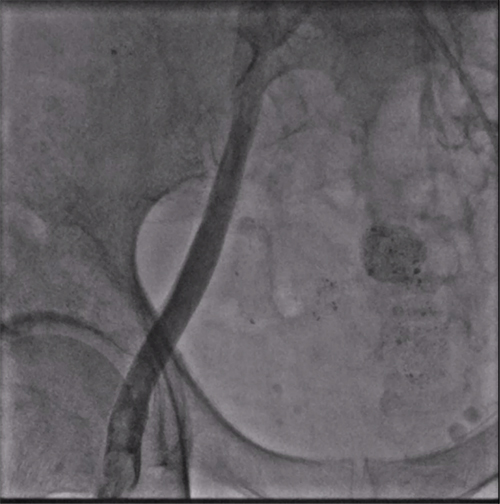

经过周密的术前准备,彭晖、孙志军两位主任带领邸北冰主治医师、柳晓娜主治医师和梁立丰医师在内的起搏电生理团队,于心脏介入手术室为患者实施手术。手术团队股静脉穿刺成功后,首先对下腔静脉进行造影并将外鞘放置送入下腔静脉,随后将新型主动固定螺旋无导线起搏器顺利跨瓣送入右心室目标位置,旋入前测试无导线起搏器各项电学参数良好,确认位置合适后旋入固定起搏器,在植入过程中动态测试起搏器各项参数以辅助判断固定程度,达到标准后进入对接栓模式,再次测试起搏器固定位置稳定、各项参数良好后释放起搏器,最后撤出鞘管,顺利完成手术。整个手术流程高效有序,医疗团队成员紧密配合,默契无间,仅耗时40分钟共同完成了这一具有挑战性的任务。

股静脉穿刺后下腔静脉造影